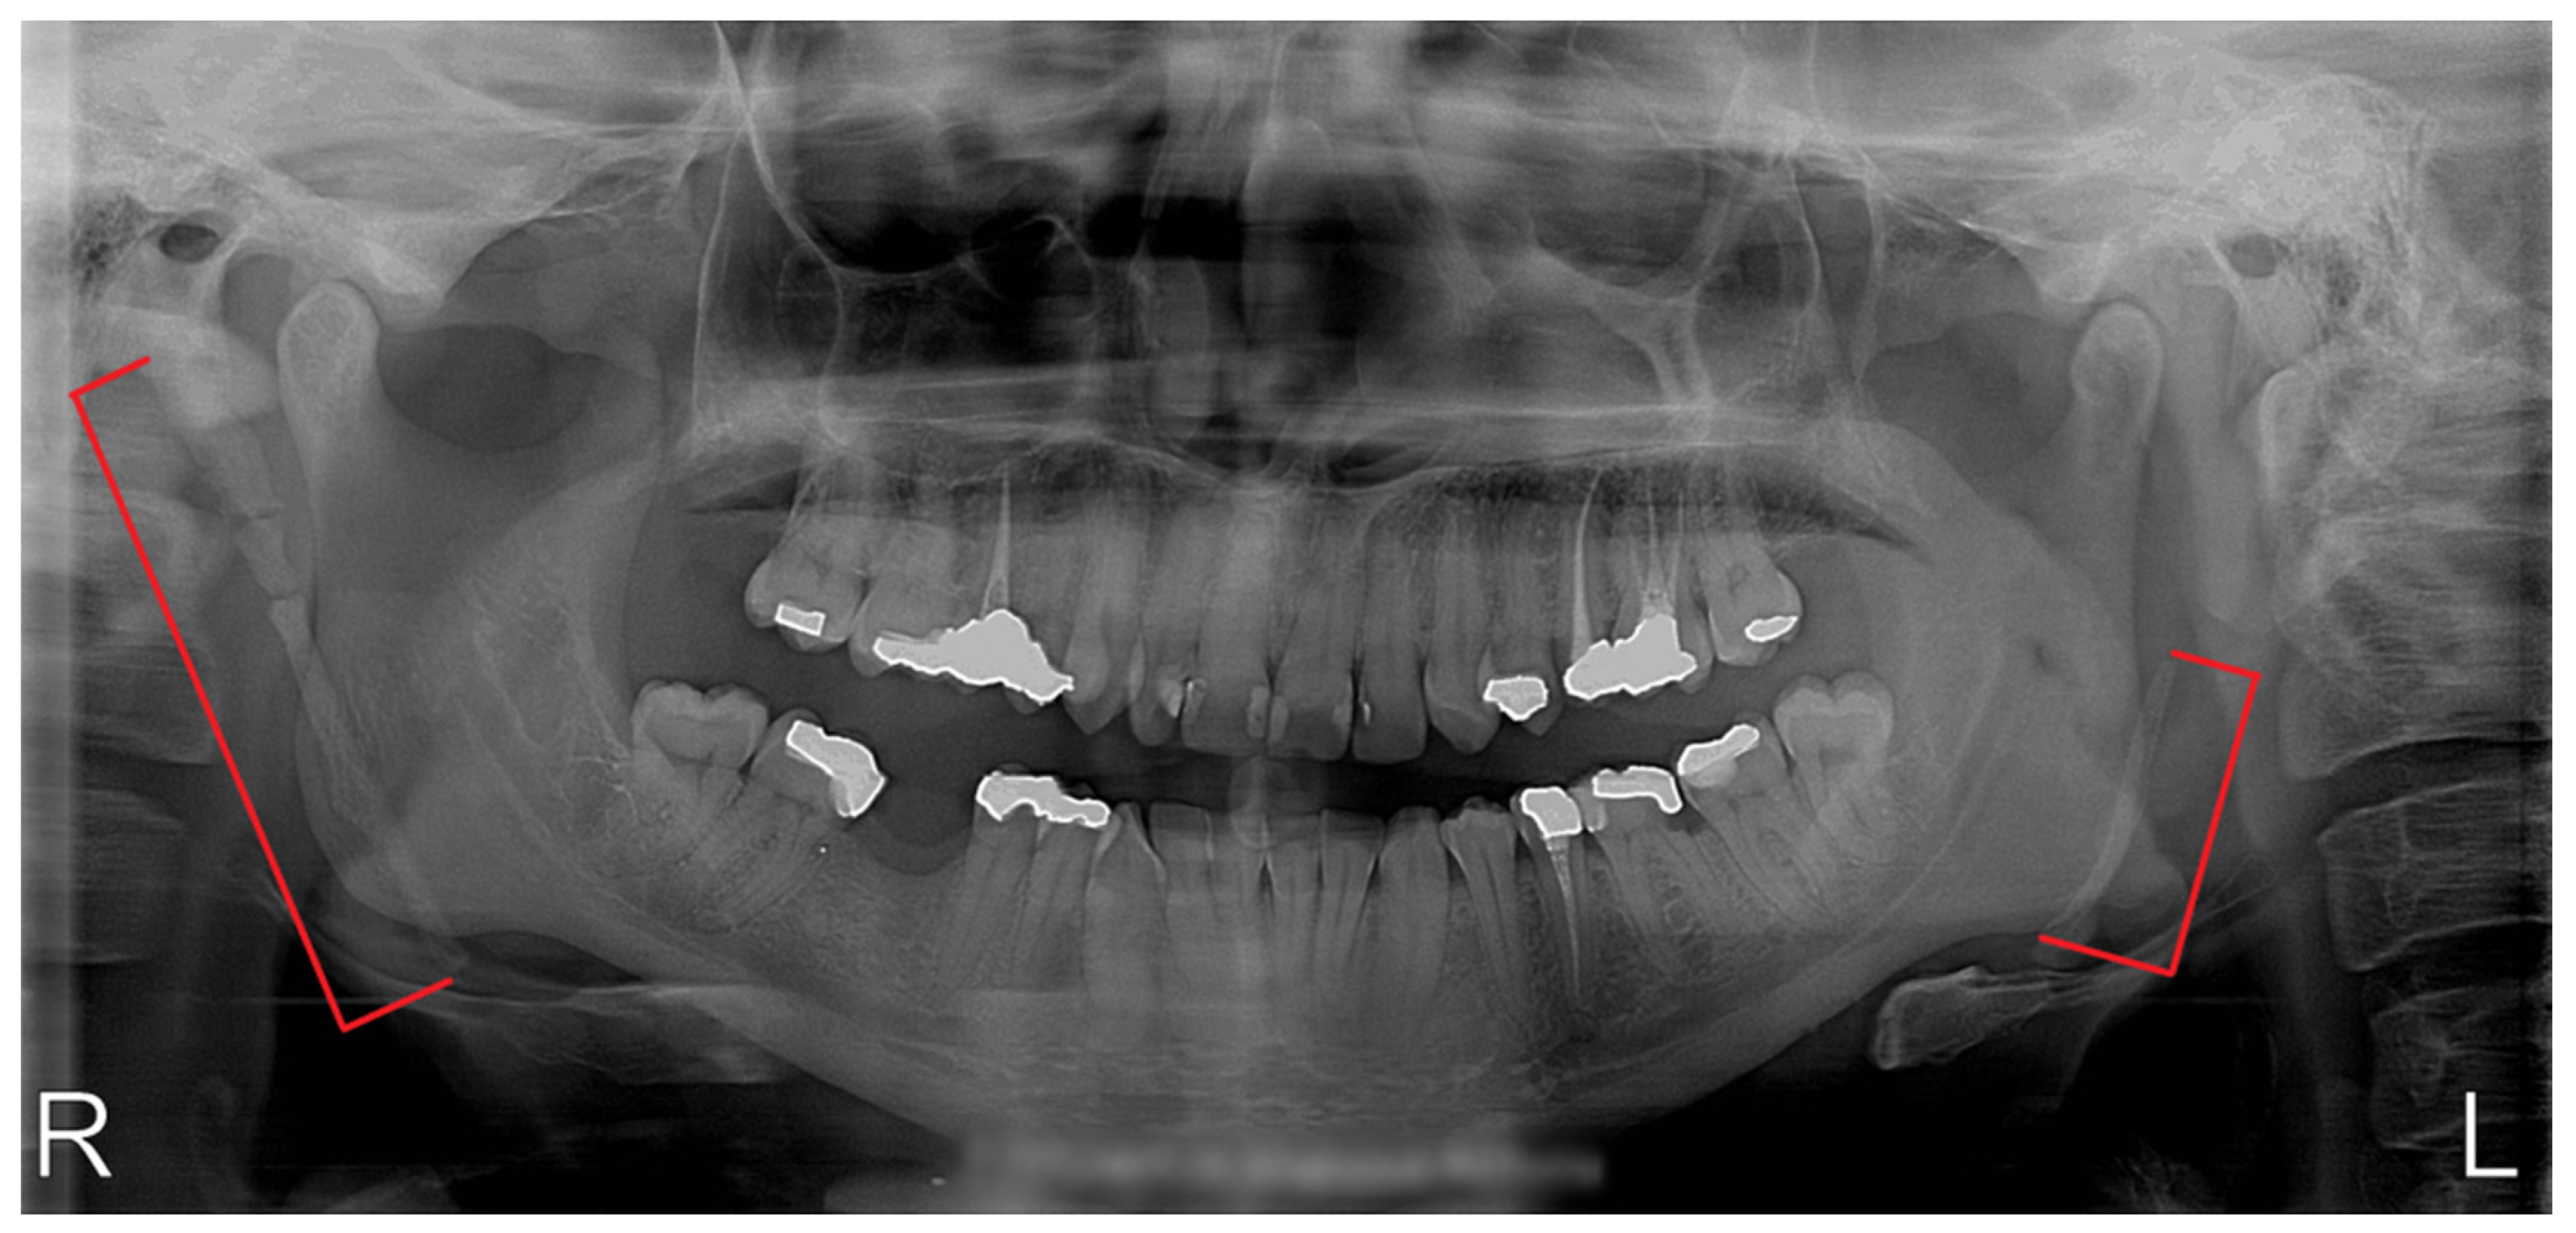

Between 2018 and 2019, five patients (age 44–77 year; 3 females and 2 males) were admitted to the Department of Oral and Maxillofacial Surgery, Faculty of Medicine, Comenius University in Bratislava, Slovakia, with 1–3-year history of bilateral or unilateral throat pain, otalgia and pharyngeal foreign body sensation. Two patients presented with dominant symptoms of dysphagia and pharyngeal foreign body sensation, one patient reported only bilateral neck pain with otalgia, one patient reported particularly unilateral neck pain accompanied by hypersalivation and voice change lasting for a few minutes after head rotation and one patient presented with symptoms of carotid compression—presyncope after rotating the head to the left. All patients had tried several courses of anti-inflammatory medication and multiple antibiotic therapies without sufficient effect. In all cases, a complete head and neck examination was performed (intraoral, extraoral); radiographic analysis (panoramic radiograph and computer tomography examinations, Figure 2 and Figure 3) of the head and neck region were obtained, and two patients underwent fiber optic laryngoscopy (due to foreign body sensation). Based on the clinical manifestations, radiological findings and digital palpation of the process in the tonsillar fossa, the diagnosis of Eagle´s syndrome was established. Four patients had bilateral elongation of the styloid process, and one patient was diagnosed unilaterally.

Figure 2.

Panoramic radiograph of a patient with bilateral elongation of the styloid process.